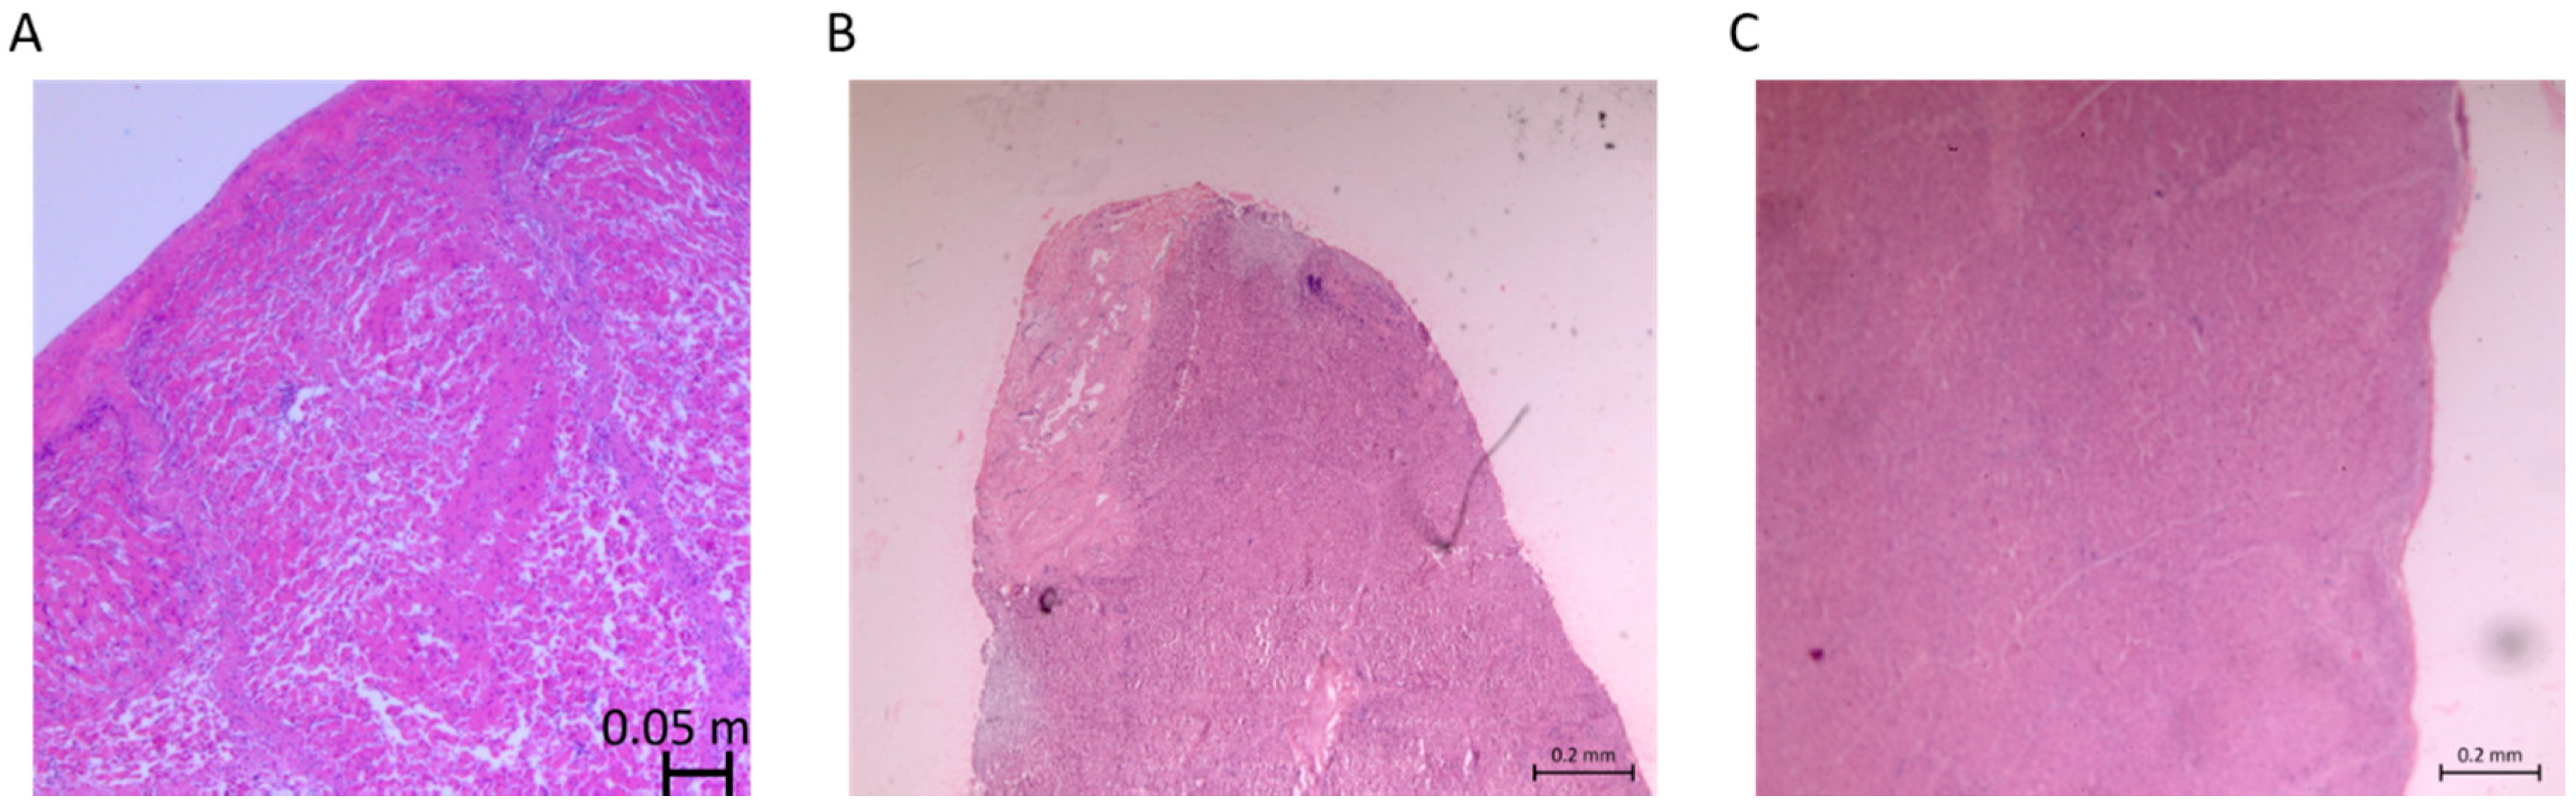

3.3. Variability in Injury Magnitude: Eschar Diameter

3.4. Variability in Injury Magnitude: Depth of Injury